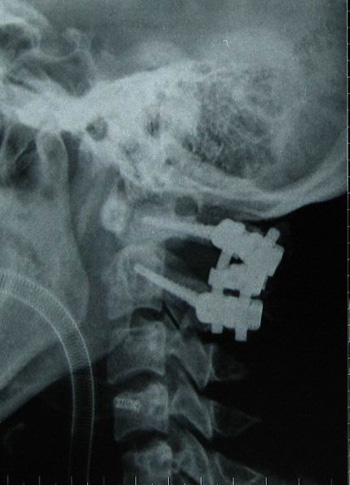

术后x线片

|